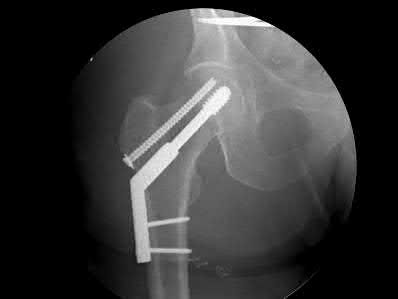

A 76-year-old male community ambulatory presented to clinic complaining of pain in the left groin that has been persistent for the last 8 months. Radiographs obtained from clinic are seen in Figure A. You suspect a femoral neck nonunion and obtain a CT scan which confirmed it. Which of the following statements is true?

A total hip arthroplasty (THA) after nonunion of a femoral neck fracture would provide the best long term outcomes in a 76-year-old male who is a community ambulator.

After nonunion of a femoral neck fracture, hemiarthroplasty and THA are good salvage option for the physiologically older patients. When deciding between these two options, THA is better for active and cognitively intact patients. THA is also indicated in patients with radiographic evidence of degenerative disease about the acetabulum. Hemiarthroplasty is advocated for patients who are older and less active.

Yang et al. retrospectively investigated the risk factors for nonunion in patients treated with cannulated screws. They reviewed 202 patients who had femoral neck fractures and were treated with internal fixation with cannulated screws. They identified that triangle configuration, displaced fracture, borderline or unacceptable reduction, and increased screw shaft subchondral purchase over the femoral neck were all risk factors for nonunion after internal fixation.

Inverted triangle configuration was found to increase rate of union.

Archibeck et al. retrospectively reviewed the outcomes of 102 THAs after failed internal fixation for a hip fracture (including both femoral neck and intertrochanteric). They concluded that the conversion of failed hip internal fixation has elevated risks compared to a primary THA, however, it may still be successful. The biggest concern for these patients postoperatively are periprosthetic fracture and dislocation.

Figures and Illustrations:

Figure A is an AP pelvic radiograph demonstrating a nonunion of a femoral neck fracture after suboptimal fixation with 3 cannulated screws in a triangle configuration.

Illustration A is an AP radiograph of the left hip in this patient following conversion to THA.

Illustration B is a radiograph demonstrating a valgus osteotomy. Illustration C shows an example of a femoral neck nonunion with varus malreduction.

Incorrect Answers:

Answer 2: Varus reduction is closely correlated with failure in this fixation method.

Answer 3: The patient's best outcome would be with THA.

Answer 4: This would be a good option in a younger patient, but given age and functional capacity, the best option is THA.

Answer 5: Patients with hemiarthroplasty have lower rates of dislocation.